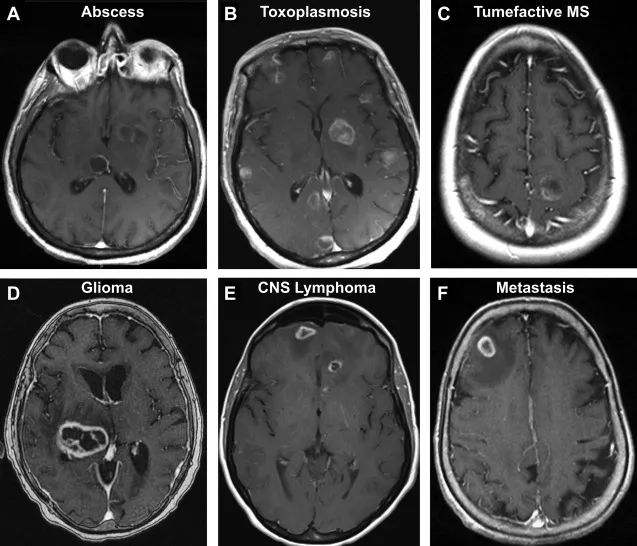

- Diagnosis: Ring-enhancing lesion on CT/MRI with contrast. Restricted diffusion on DWI is key.

⭐ The central core of a bacterial abscess shows restricted diffusion on DWI MRI, helping to distinguish it from a necrotic tumor which typically does not.